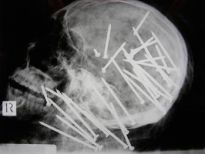

Çin'de yaşayan bu yaşlı adamın karısından çektiğini hiçbir erkek çekmemiştir herhalde. 66 yaşındaki Lin'in eşi, kumar ve alkol alışkanlığından şikayet edip duruyordu. Bir gün adam çok alkollüyken kafasına çivi bile çaktı.